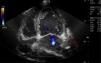

La miocardiopatía no compactada es una entidad poco frecuente asociada a complicaciones como insuficiencia cardiaca, fenómenos cardioembólicos, arritmias y muerte súbita. De etiología del todo no aclarada, presenta una base genética. Su diagnóstico está aumentando debido al uso de la ecocardiografía, y se caracteriza por el engrosamiento de la pared del ventrículo izquierdo con prominencias y recesos con ausencia de compactación del miocardio, diferenciándose dos capas: miocardio compactado y no compactado (fig. 1). Es característico visualizar en Doppler color de flujo sanguíneo entre dichas criptas sin comunicación con el sistema coronario (figs. 2 y 3), pudiendo originar embolias.